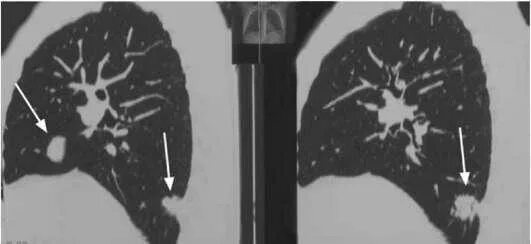

Метастазы рака почки